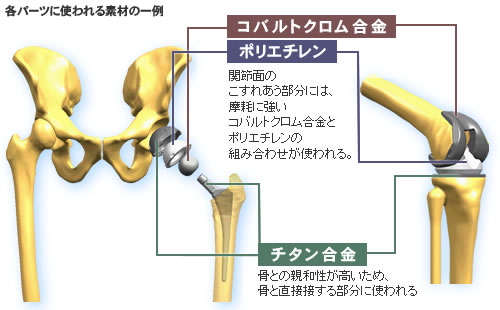

人工股関節置換術−MISから再置換まで応用できる手技のコツ [DVD付] (OS NOW Instruction) | 岩本 幸英 |本 | 通販 | Amazon, コラム27 人工関節メーカーに伺いました|人工関節コラム|人工関節とは|人工関節ドットコム,

コラム27 人工関節メーカーに伺いました|人工関節コラム|人工関節とは|人工関節ドットコム, 人工股関節置換術と人工骨頭置換術 | 世田谷人工関節・脊椎クリニック,